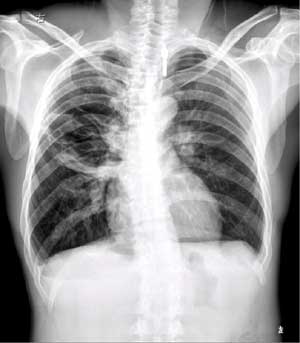

以下是引用向医生在2004-6-30 20:21:28的发言:[br]右上肺有多个薄壁囊状透亮区,其内无明显液平面.[br]意见:右上肺多发性肺囊肿.